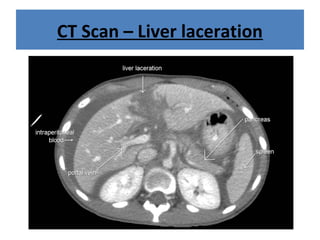

CT Scan – Liver laceration

CT Scan –Liver laceration